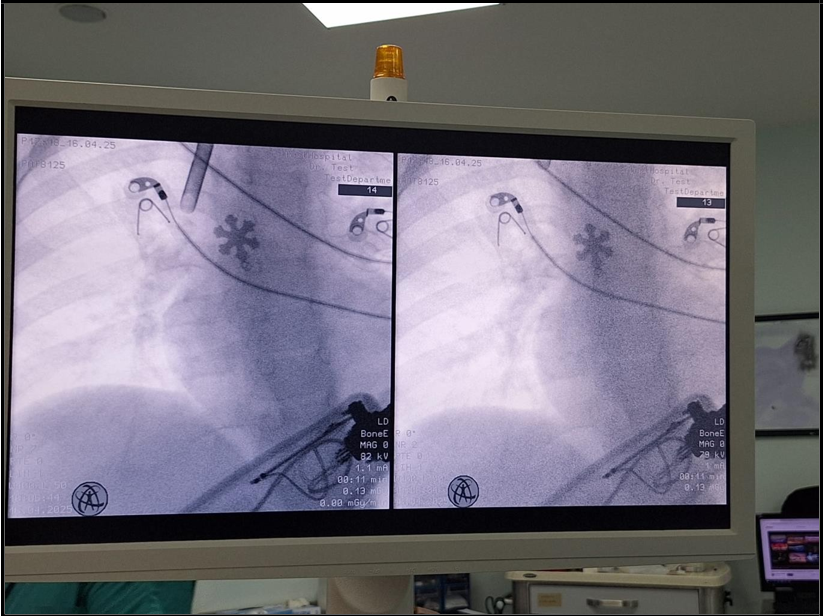

The surgeon attempted rigid bronchoscopy, although the first attempt was unsuccessful, and the patient experienced severe desaturation with SpO₂ dropping to 40%. Immediate mask ventilation was provided, which restored oxygenation. A second attempt at rigid bronchoscopy was then successfully performed, leading to removal of a snowflake-shaped pendant from the right main bronchus (Figure 2). In order to reduce the risk of post-procedural airway edema, prednisolone 1 mg/kg was administered intravenously.

Figure 2: Snowflake-shaped pendant removed from the right main bronchus during rigid bronchoscopy.